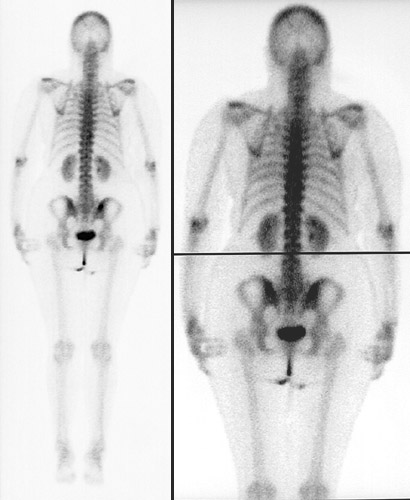

| These composite images in a posterior view above and anteriorly below represent the normal appearance of a bone scan using Tc99. The areas of uptake are even and symmetrical. The only "hot spots" appear in the posterior iliac crests as a consequence of recent bone marrow biopsies. The bladder is also highlighted, along with the catheter, because of excretion of the radioisotope through the kidneys, which are outlined as well. |